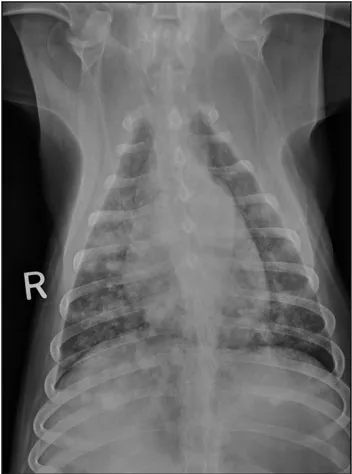

CASE 1.1 A 7-year-old neutered male Labrador Retriever who was hit by a car. You obtain these thoracic radiographs: Figs. 1.1a, b, left and right lateral projections, respectively; Figs. 1.1c, d, ventrodorsal and dorsoventral projections, respectively.

1.1a